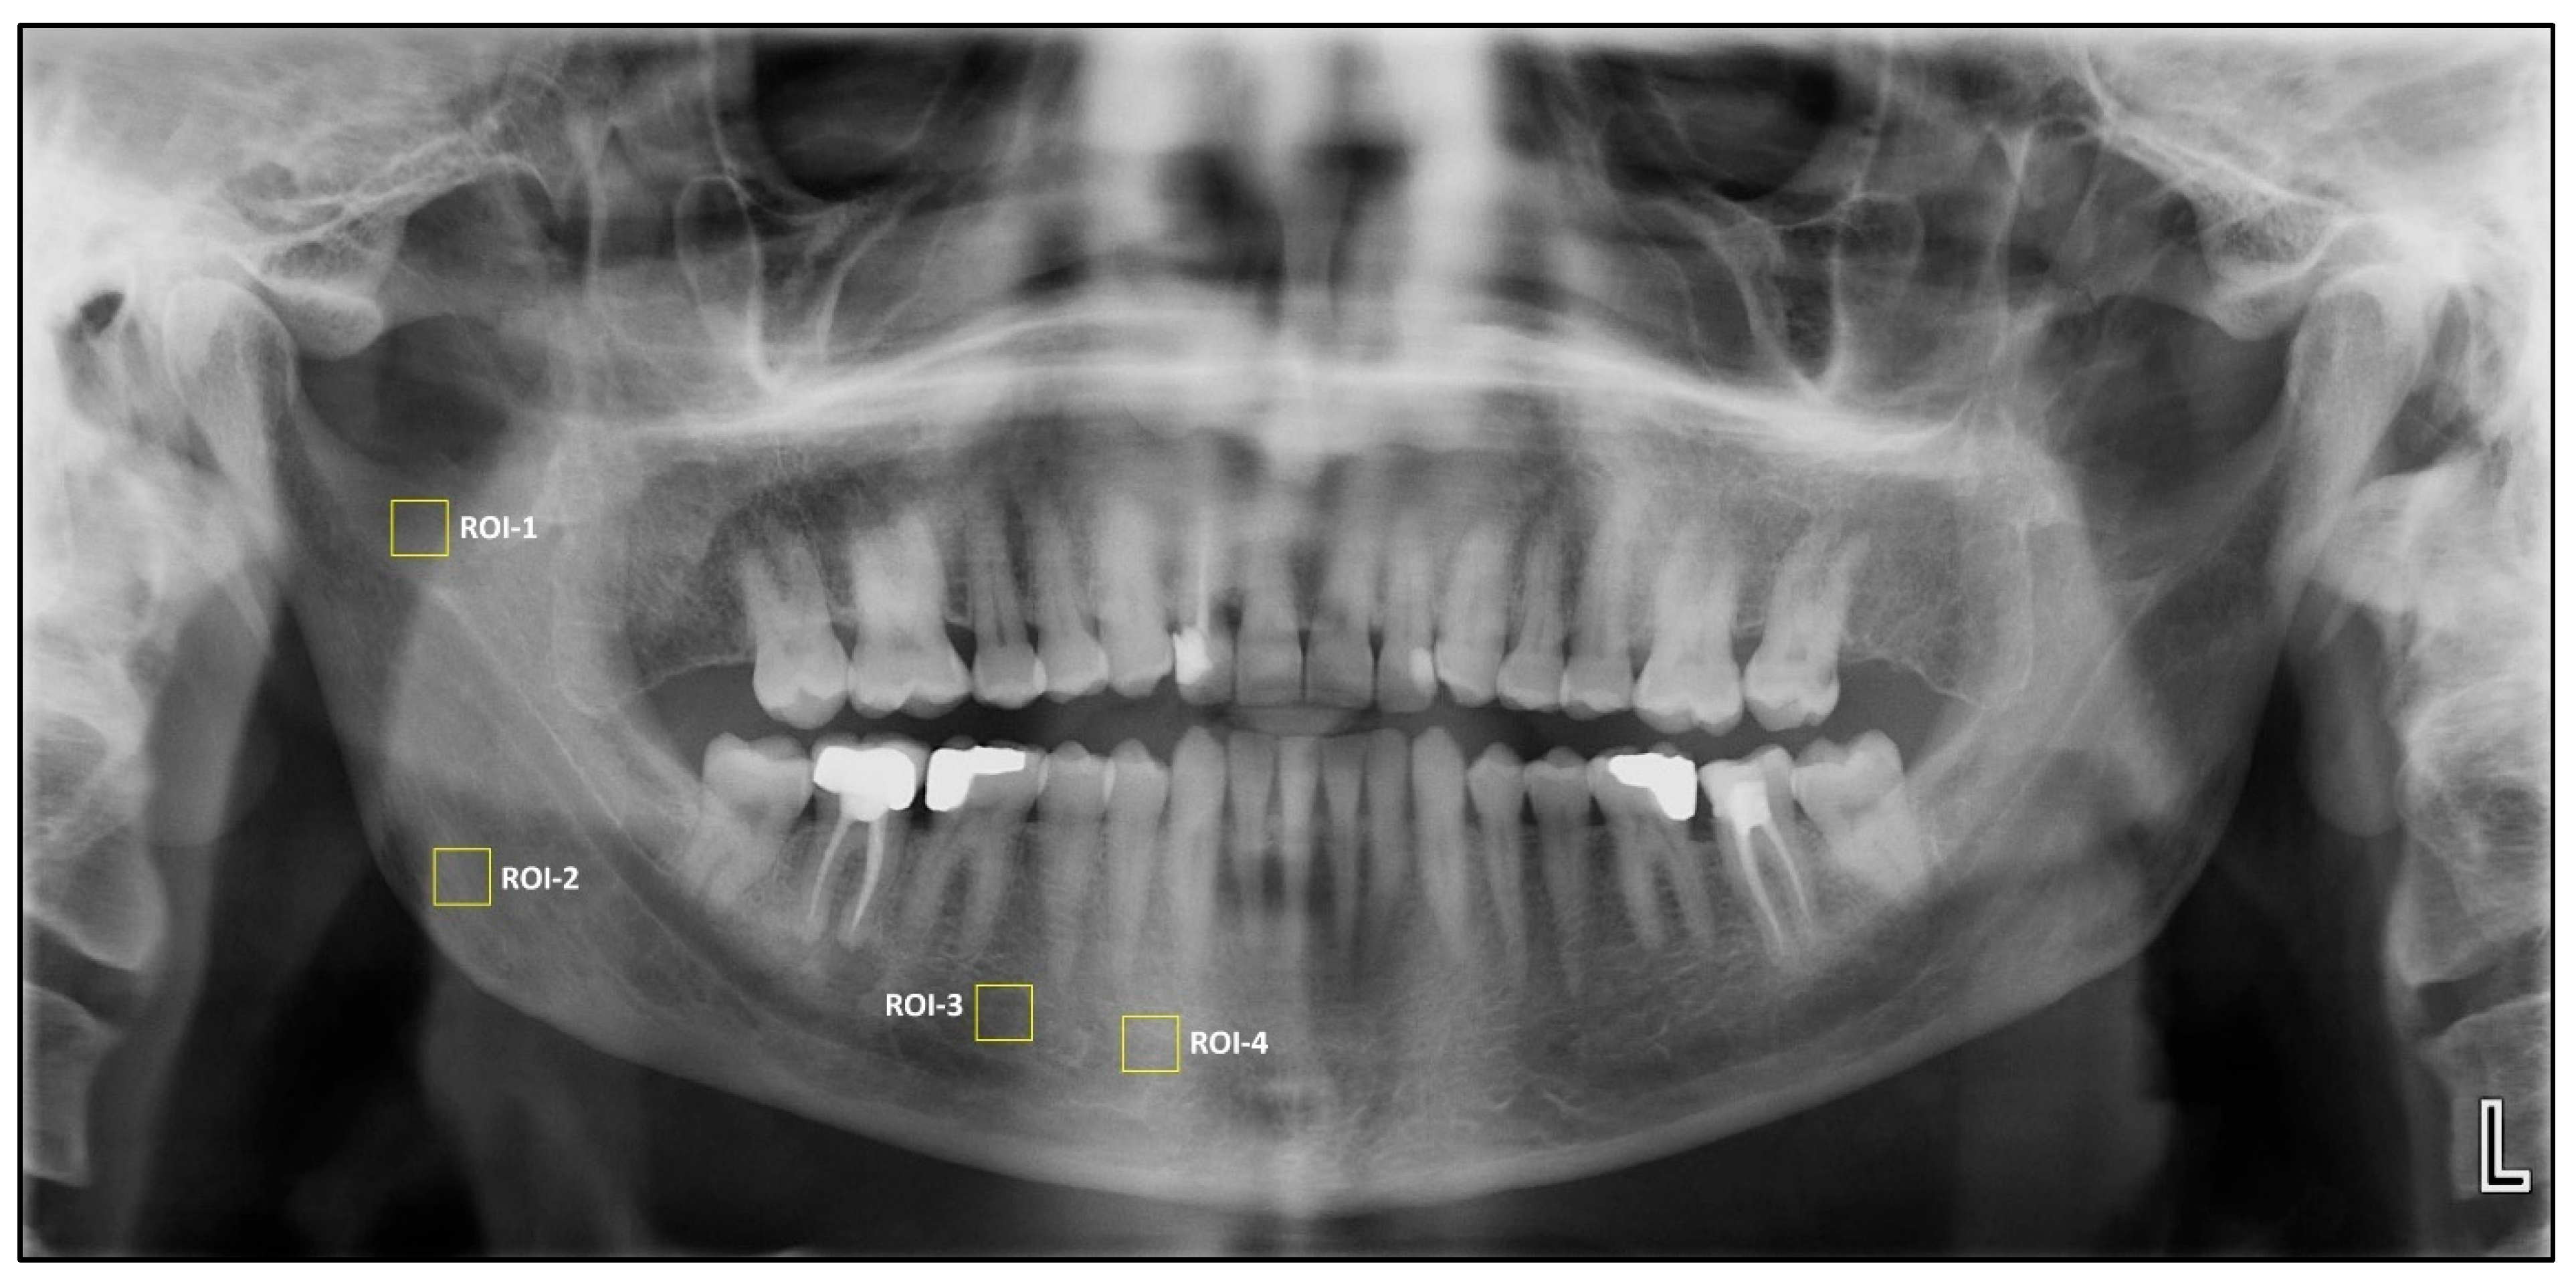

Square regions of interest (ROIs) of 64 × 64 pixels were selected owing to their frequent use in previous studies [13]. Four square ROIs were then placed on the right side of the mandible for fractal dimension and histogram-based pixel intensity analyses performed on dental panoramic radiographs. ROI1 was defined at the geometric center of the area between the mandibular notch and the mandibular foramen. ROI2 was positioned in the supracortical region superior to the mandibular angle. ROI3 was placed distal to the apex of the second premolar, carefully avoiding the mandibular canal’s cortical borders, periodontal ligament space, lamina dura, and root apices. ROI4 was located anterior to the mental foramen, excluding adjacent anatomical structures.

Figure 1.

Selection of region of interest (ROIs).